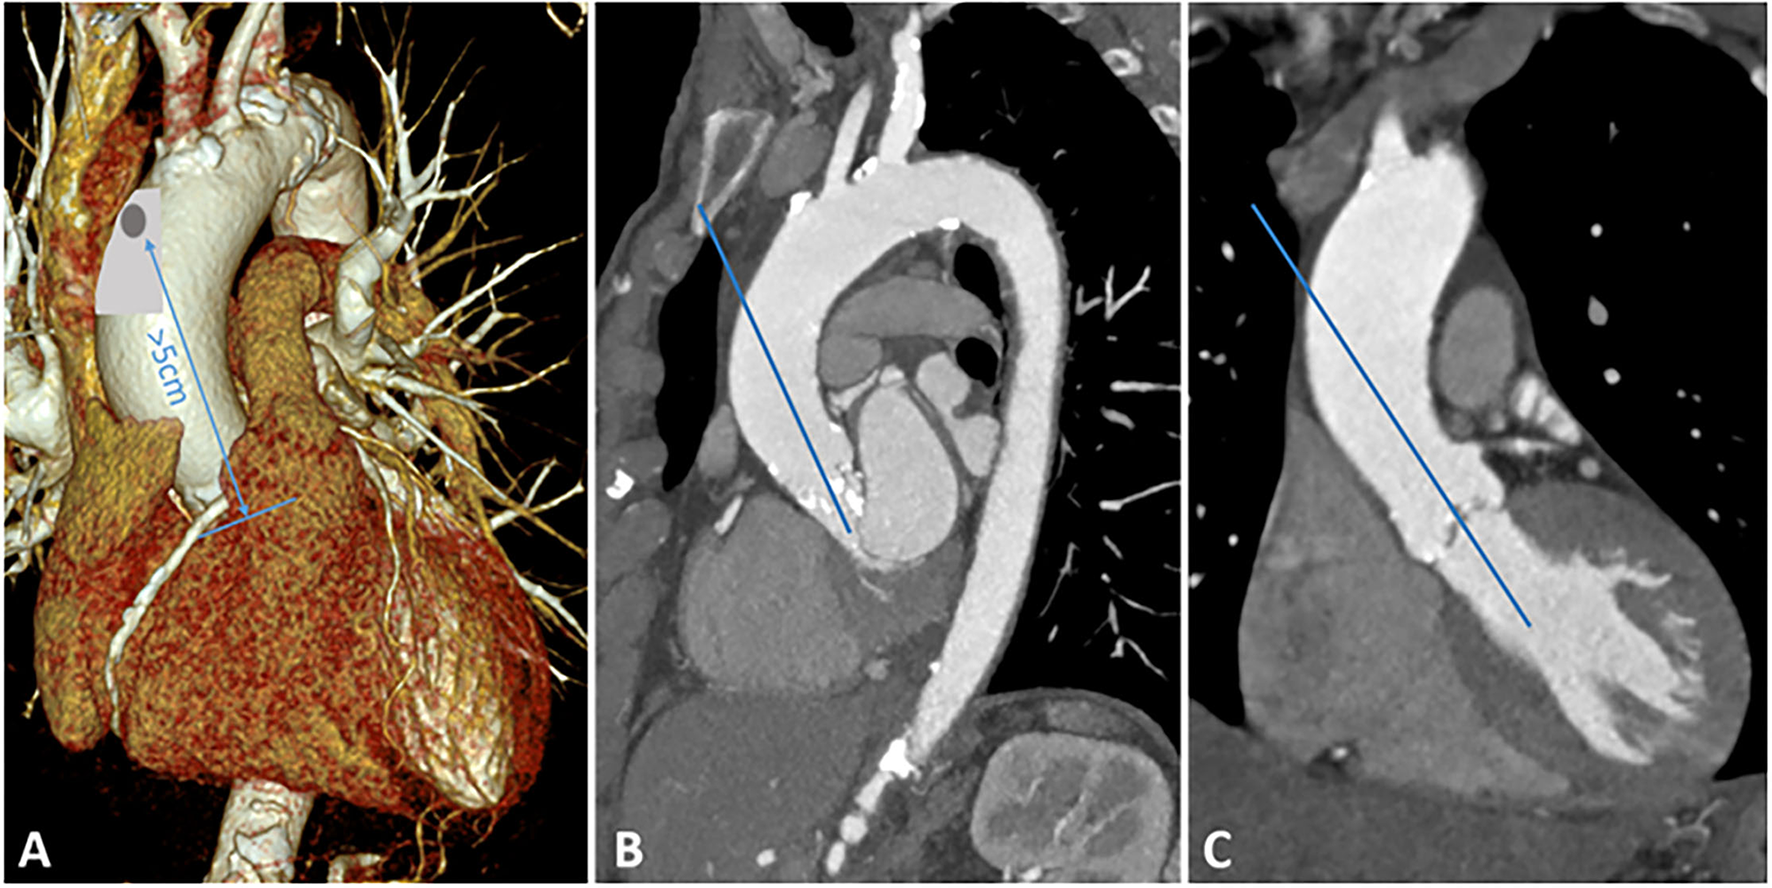

After a longitudinal incision of the pericardium, the ascending aorta can be exposed very easily. Identification of a suitable location is crucial: the puncture should be more than 5 cm away from the aortic annulus. In addition, the angle of puncture should be in line with the left ventricular outflow tract. In most cases, the anterolateral part of the ascending aorta is well applicable. Figure 1 illustrates the most appropriate location for aortic puncture to achieve the desired angle in the aortic root. In the next step, the ascending aorta is gently manipulated to identify atherosclerotic deposits, which should be avoided as an entry point. Two circular purse strings are placed on the selected spot with 3-0 prolypropylene.

Figure 1

Preoperative MSCT. (A) 3D reconstruction of the aortic arch, appropriate location for aortic puncture is highlighted in gray. The distance between the puncture and the aortic annulus should be at least 5 cm. (B) Sagittal plane of the aortic arch. (C) Coronary plane of the ascending aorta.